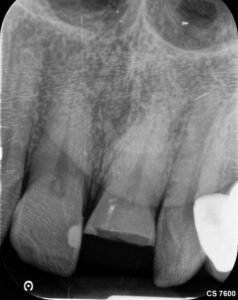

In diesem Fall geht es um einen männlichen Patienten, 54, Diabetes mellitus, leichter Raucher. Er ist seit 2016 Stammpatient im Haus. Der Patient wurde intern zur Wurzelkanalbehandlung überwiesen. Der Schneidezahn 21 wies nach einem Trauma eine unkomplizierte Kronenfraktur in Höhe der Schmelz-Zement-Grenze auf. Der Patient wurde bei AllDent Frankfurt am Karfreitag 2025 im Notdienst erstversorgt. Das Bruchstück konnte sowohl im Notdienst als auch bei der Kontrolluntersuchung bei seinem Stammbehandler, Ans Tawel (M.Sc) am 9. Mai wieder befestigt werden.

Vier Wochen nach der Erstversorgung erschien der Patient zur Wurzelkanalbehandlung. Der Schneidezahn 21 war zu dem Zeitpunkt noch vital. Der Patient klagte allerdings über immer häufiger werdende Schmerzintervalle sowie zunehmende Reaktionen auf Wärme. Das Parodontium zeigte sich ohne pathologischen Befund mit Sondierungstiefen bis drei Millimeter. Über die Fraktur hinausgehende Verletzungen wurden im Notdienst nicht dokumentiert und konnten zum Behandlungstermin ebenfalls nicht diagnostiziert werden.